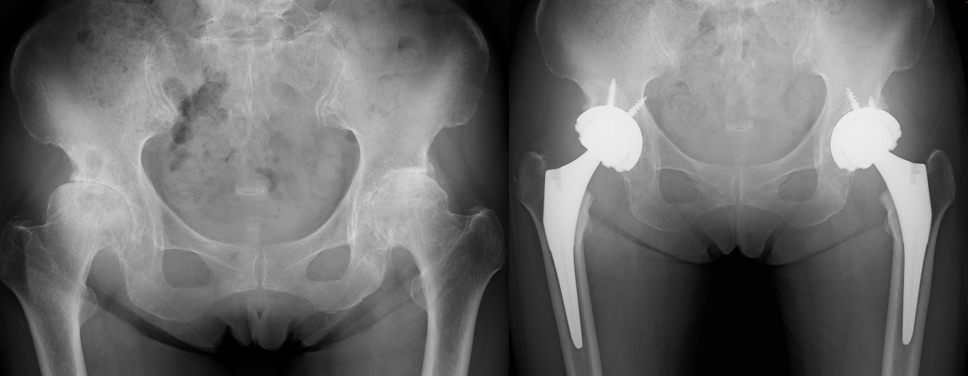

変形性股関節症は原因が特定できない一次性と、様々な疾患により関節軟骨が変性・摩耗して生じる二次性に分類されます。わが国では臼蓋形成不全による二次性変形性股関節症が多い傾向があります。

まずは理学療法や投薬治療により疼痛改善と活動度の拡大を目指しますが、関節軟骨が摩耗し骨変形が悪化し疼痛が増悪してしまった末期股関節症に対して、人工関節全置換術を行っております。

当院では両側変形性股関節症に対して両側同時人工股関節全置換術を積極的に行なっております。一度の入院で手術を安全に終えることができ、経済的にも時間的にも負担軽減につながります。両側同時の手術も片側と同様に術後1日目より離床することができます。リハビリテーションの進行は手術前の状態によって個人差はありますが、退院時には日常生活の質の向上が期待できます。

【X線(左写真:両側末期変形性股関節症、右写真:両側同時人工股関節全置換術後)】